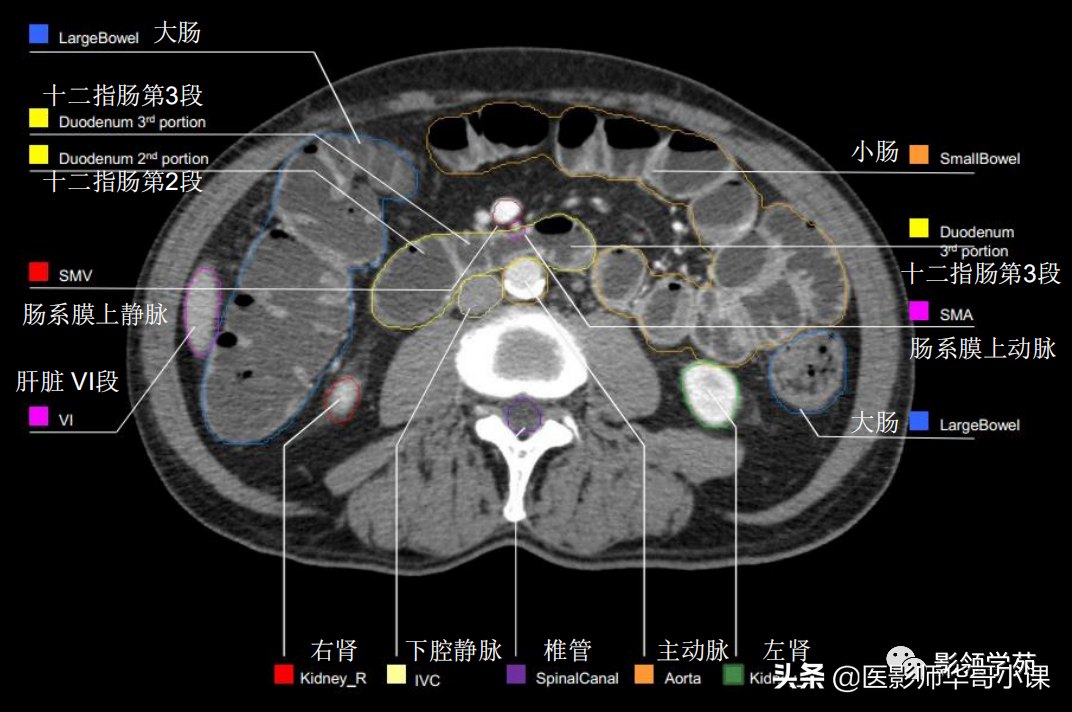

解剖专题腹部横断位解剖详细标注肝脏分段